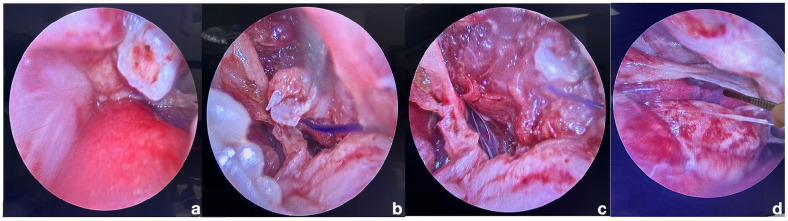

病例总结:一只11岁的雄性绝育家长毛猫在被狗袭击后胸部严重受伤,被送到紧急转诊医院。最初的稳定包括补充氧气、静脉输液、即时超声(POCUS)、连续血气分析、胸部和腹部x光片、阿片类镇痛药和广谱抗生素。CT显示多发内移位肋骨骨折,穿透纵隔,靠近颅腔静脉和主动脉弓近端。采用视频辅助胸腔镜手术(VATS),在2.7 mm 0°短腹腔镜下,经皮缝合放置特制玻璃纤维夹板,准确复位肋骨骨折碎片,避免进一步损伤胸内结构。夹板固定了6周。在第8周复查时,猫没有心血管或呼吸损伤的迹象,能够恢复正常活动。术后14个月进行长期随访电话随访。业主报告说,病人一直很好,没有任何并发症。相关性和新信息:据作者所知,这是第一个使用VATS治疗猫创伤性肋骨骨折的报道。本病例强调了该方法的可行性和成功,是未来临床病例的可行选择。

Case summary: An 11-year-old male neutered domestic longhair cat was presented to an emergency referral hospital after sustaining severe injuries isolated to the thorax after a dog attack. Initial stabilisation included oxygen supplementation, intravenous fluid therapy, point-of-care ultrasound (POCUS), serial blood gas analyses, thoracic and abdominal radiographs, opioid analgesics and broad-spectrum antibiotics. CT revealed multiple internally displaced rib fractures that punctured through the mediastinum and were in intimate proximity to the cranial vena cava and proximal aortic arch. Video-assisted thoracoscopic surgery (VATS) was performed using a 2.7 mm 0° short laparoscope to place a custom-made fibre glass splint via percutaneous suturing to accurately reduce the rib fracture fragments without further damage to the intrathoracic structures. The splint remained in place for 6 weeks. At the 8-week recheck, the cat had no evidence of cardiovascular or respiratory compromise and was able to resume normal activity. A long-term follow-up phone call was conducted at 14 months postoperatively. The owner reported that the patient has continued to do well without any complications.